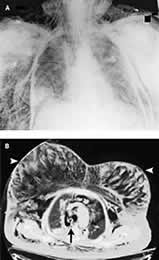

1例77岁妇女接受T12至S1椎板切除术和后脊柱融合术,手术取俯卧位,手术结束后改为仰卧位,送入重症监护病房,此时病人气道压力快速升高,出现大块皮下气肿和低氧血症。胸部X线显示有皮下气肿,但无明显气胸(图A)。放置双侧胸导管但病人的低氧血症无改善。CT扫描显示有大量皮下气肿(图B),并确认在气管隆突上2 cm(箭头)有一气管穿孔,与纵隔积气和气胸相关。推测此气管穿孔由气管插管所致,它易于发生在从俯卧位变为仰卧位时。病人随后接受了胸廓切开术,修复气管损伤,此后病人康复。, http://www.100md.com(苏晓 摘译自N Engl J Med(2004;352:e2)